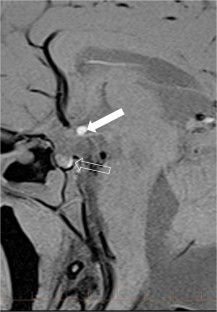

We selected pediatric head MRI examinations from 2005 to 2017 based on the finding of a double midline sellar and suprasellar bright spot on T1-weighted sequence. Medical history, physical examination, pituitary hormonal profile and bone age evaluation were extracted from the medical record of the selected patients. An experienced pediatric neuroradiologist reviewed head MRIs, which were performed on 3-tesla (T) magnet and included at least sagittal T1-weighted imaging centered on the sella turcica obtained with and without fat suppression.

In six cases, two midline bright spots were identified on T1-weighted sequences obtained both with and without fat suppression. While one spot was located at the expected site of the neurohypophysis in the posterior sella, the second one was in the region of the median eminence, suggesting partial ectopic posterior pituitary gland. Growth hormone deficiency, either isolated (n=1) or combined with thyroid stimulating hormone deficiency (n=1) was found. None of the children had clinical signs of posterior pituitary dysfunction.

Fig. 4